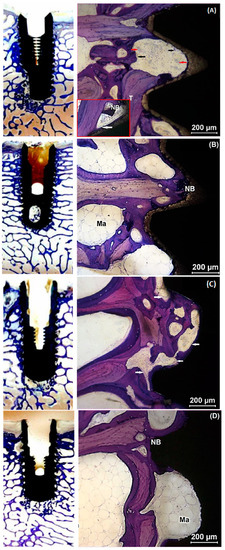

2.4. Histological Evaluation